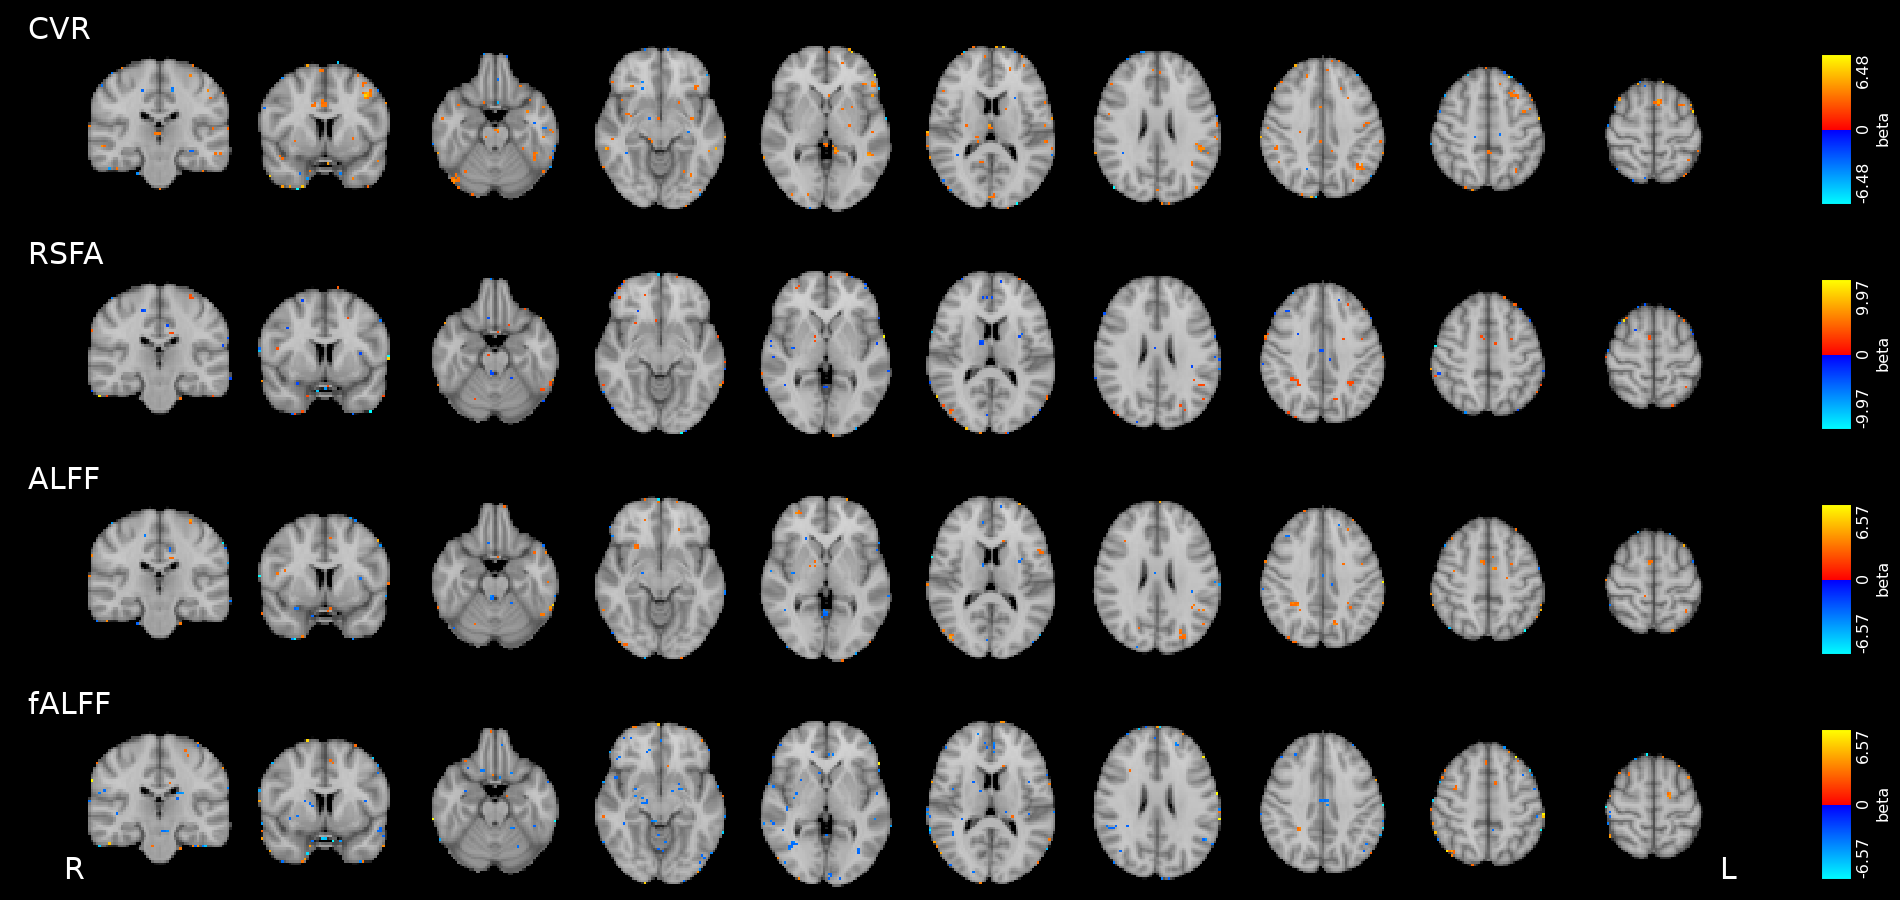

Results: CVR and RSF

Physiology and RSF

We used 3dLMEr¹ to set up the following LME models (R syntax):

Effect of Sex

Only sex had a significant effect on RSF

Effect on CVR

Results: CVR and RSF

Golestani et al. 2016 (NeuroImage)

Results: CVR, RSF, and tasks

Motor task

Simon task, congruent responses

Simon task, incongruent responses

The relationship between CVR, RS fluctuations, and tIA

might be highly subject specific

or absent altogether.

Take home message #3

- We did not observe a statistically significant effect of CVR on RS fluctuations, or of CVR and RS fluctuations on task induced activity, most probably due to the high variability between subjects

-

The failure of generalisation of previous observations might be related to different methods, but whether this is related to a better denoising and signal quality or to a possibly non optimal setting (e.g. compared to gas challenges) is uncertain

-

A different statistical perspective (i.e. Bayesian) is required to exclude any relationship between CVR and RS fluctuations, and further analyses are required to improve the agreement between CVR and RS fluctuations

-